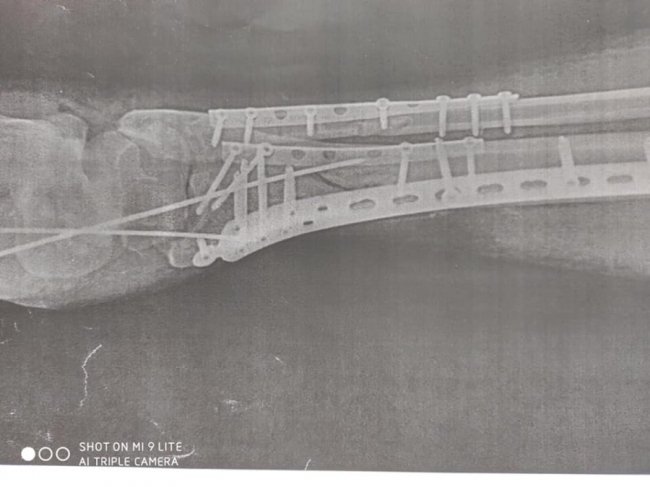

"У відділенні лікувався хворий, який впав з 4-х метрової висоти з переломом обох нижніх кінцівок. Йому успішно зробили оперативне втручання - металоостеосинтез дистальних метаепіфізів правої і лівої нижніх кінцівок з кістковою пластикою", - розповів лікар ортопед-травматолог Леонід Шеремета.

Медики міської лікарні застосовують кращі практики сучасних технологій остеосинтезу, зокрема мінімально-інвазивні методи (Minimally Invasive Plate Osteosynthesis MIPO) фіксації переломів з використанням пластин з кутовою стабільністю.

Перевагою цього методу лікування є збереження функціональної рухомості кінцівки та найближчих суглобів в період зрощення, прискорення консолідації та відновлення опорної функції кінцівки.